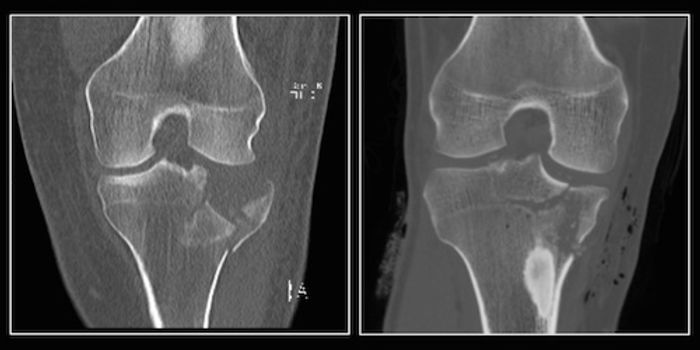

MAR 02, 2016Health & MedicineResearchers at NYU Langone Medical Center say they “have taken a frequently used and necessary imaging test and ma ...